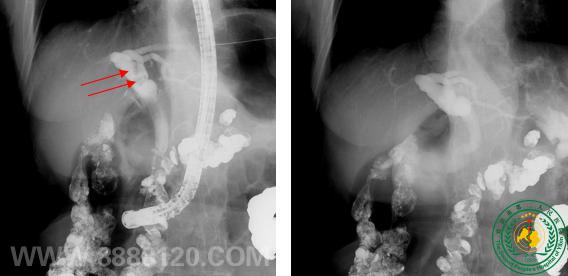

造影图像28193

宜宾市第二人民医院 图文